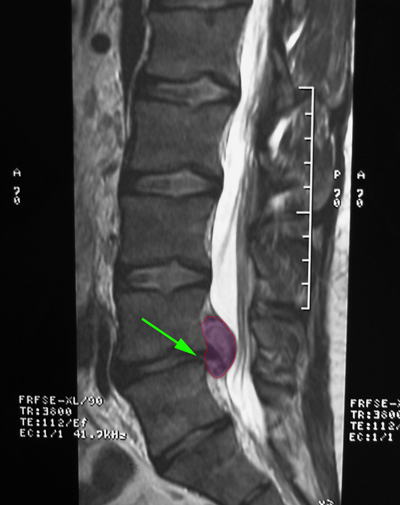

• Η Κήλη Οσφυϊκού Μεσοσπονδυλίου Δίσκου